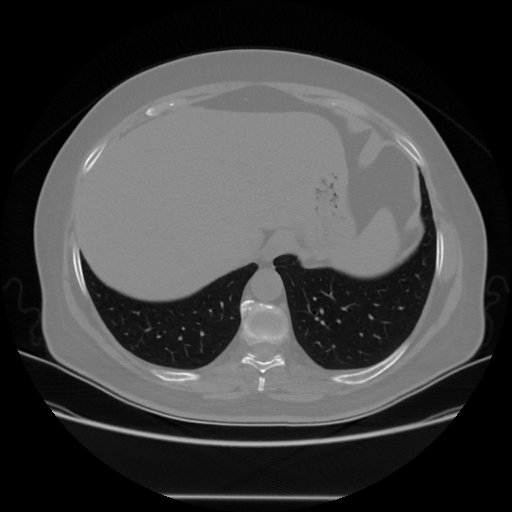

Image Grid

4Γ—3 grid: Rows show different image types (Original NATIVE, Reconstructed NATIVE, Original VENOUS, Generated VENOUS), Columns show windowing techniques (No Window, Lung Window, Mediastinum Window)

Original VENOUS CT scan

Lung window (WL -600, WW 1500 β†’ Low βˆ’1350, High +150)